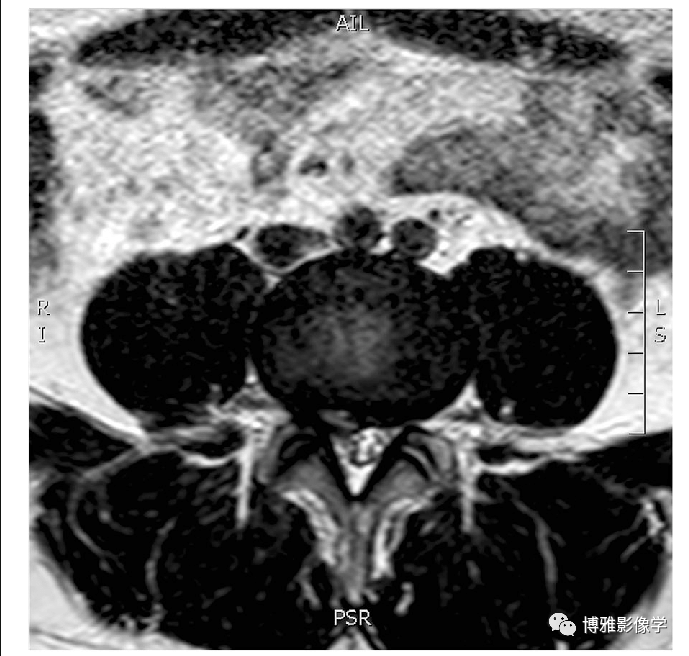

腰椎间盘突出的MSU分级分区 1a. 椎间盘突出程度分级 (1-2-3 级) 。在椎间盘最大突出的横断面进行测量,定义小关节内线(intra-facet line)为左右小关节内侧缘之间的横线。参照小关节内线,确定椎间盘突出是否延伸至或小于非突出的椎间盘后部至小关节内线距离的50%(1级),或超过该距离的50%(2级)。如果突出完全超出小关节内线,则称为3级。1级病变对神经压迫的影响较小,3级病变对神经压迫的影响最大;1b. 椎间盘突出位置分区 (A-B-C 区)。将小关节内线平均分为4等份并做垂线,左右中央象限区为A区,左右外侧象限区为B区,超出任一小关节内侧缘的区域表示C区,即超出外侧象限的边界线。突出在B区和C区的影响更大

MSU分级与分区相结合a. 2-B通常是有症状的,3-A常见于马尾综合征; b. 2-C是最大的椎间孔病变,2-AB很常见,发生在A区和B区之间。(Eur Spine J (2010) 19:1087–1093, PMID: 20084410)